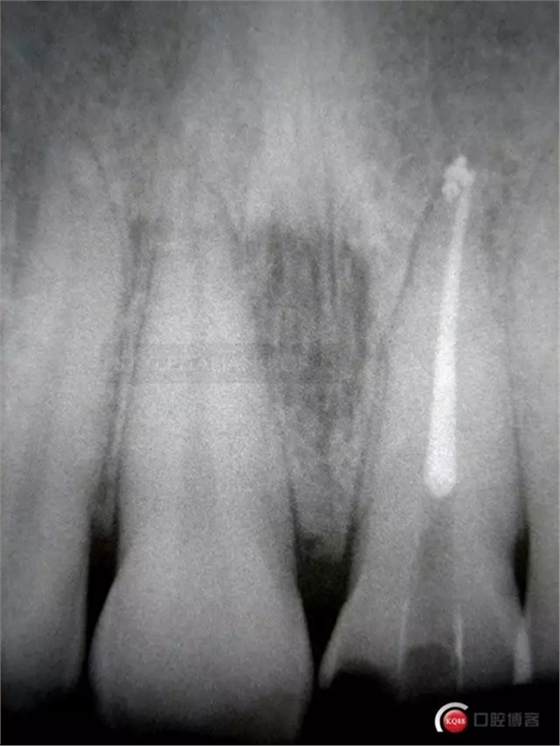

Due to the pulp hemorrhage tooth 2.1 has a discromy.

In order to prevent the external root resorption caused by a not correct bleaching approach, I put a flow barrier on the gutta-percha

Before performing an endo bleaching in office, under the dam, with 35% hydrogen peroxide and a composite stable temporary restoration with a coronal seal. Coronal seal is one of the most important factor of the clinical success during the time, because coronal bacterial infiltration are one of the main causes of failure after root canal treatment